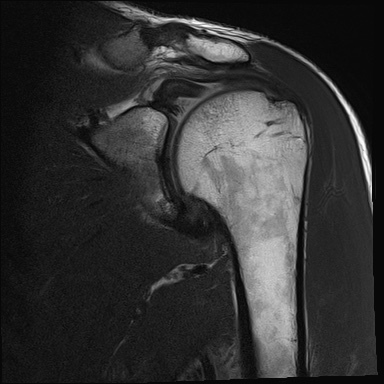

Anamese: Schulterschmerzen nach Gewichtheben. Welche Pathologien können Sie auf dem MRT der Schulter erkennen?